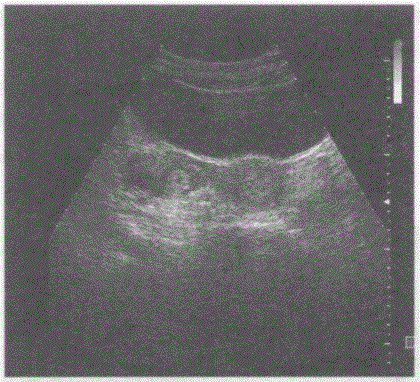

问题 临床资料:女,30岁,自诉停经40天,腹痛伴阴道出血4天。检验:尿妊娠试验阳性。 超声综合描述:子宫形态大小正常,宫腔内未见胎囊。右卵巢内见无回声,周边呈环状中强回声,CDFI:周边可见血流信号。见下图及彩图。 {图1} 超声提示:

选项 A.右卵巢异位妊娠 B.右卵巢黄体囊肿 C.右卵巢卵泡 D.右卵巢癌

答案 A